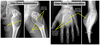

• Descreva a lesão:

A

• Osso esqueleticamente maduro

• Localizada no fêmur distal, predominantemente metafisária, acometendo medula e cortical

• Lesão única, de grande dimensão

• Lítica

• Sem padrões de conteúdo em específico

• Margens mal definidas

• Rompe a cortical medial, lateral e posterior

• Possui extensão para partes moles

• Sem reação periosteal visível